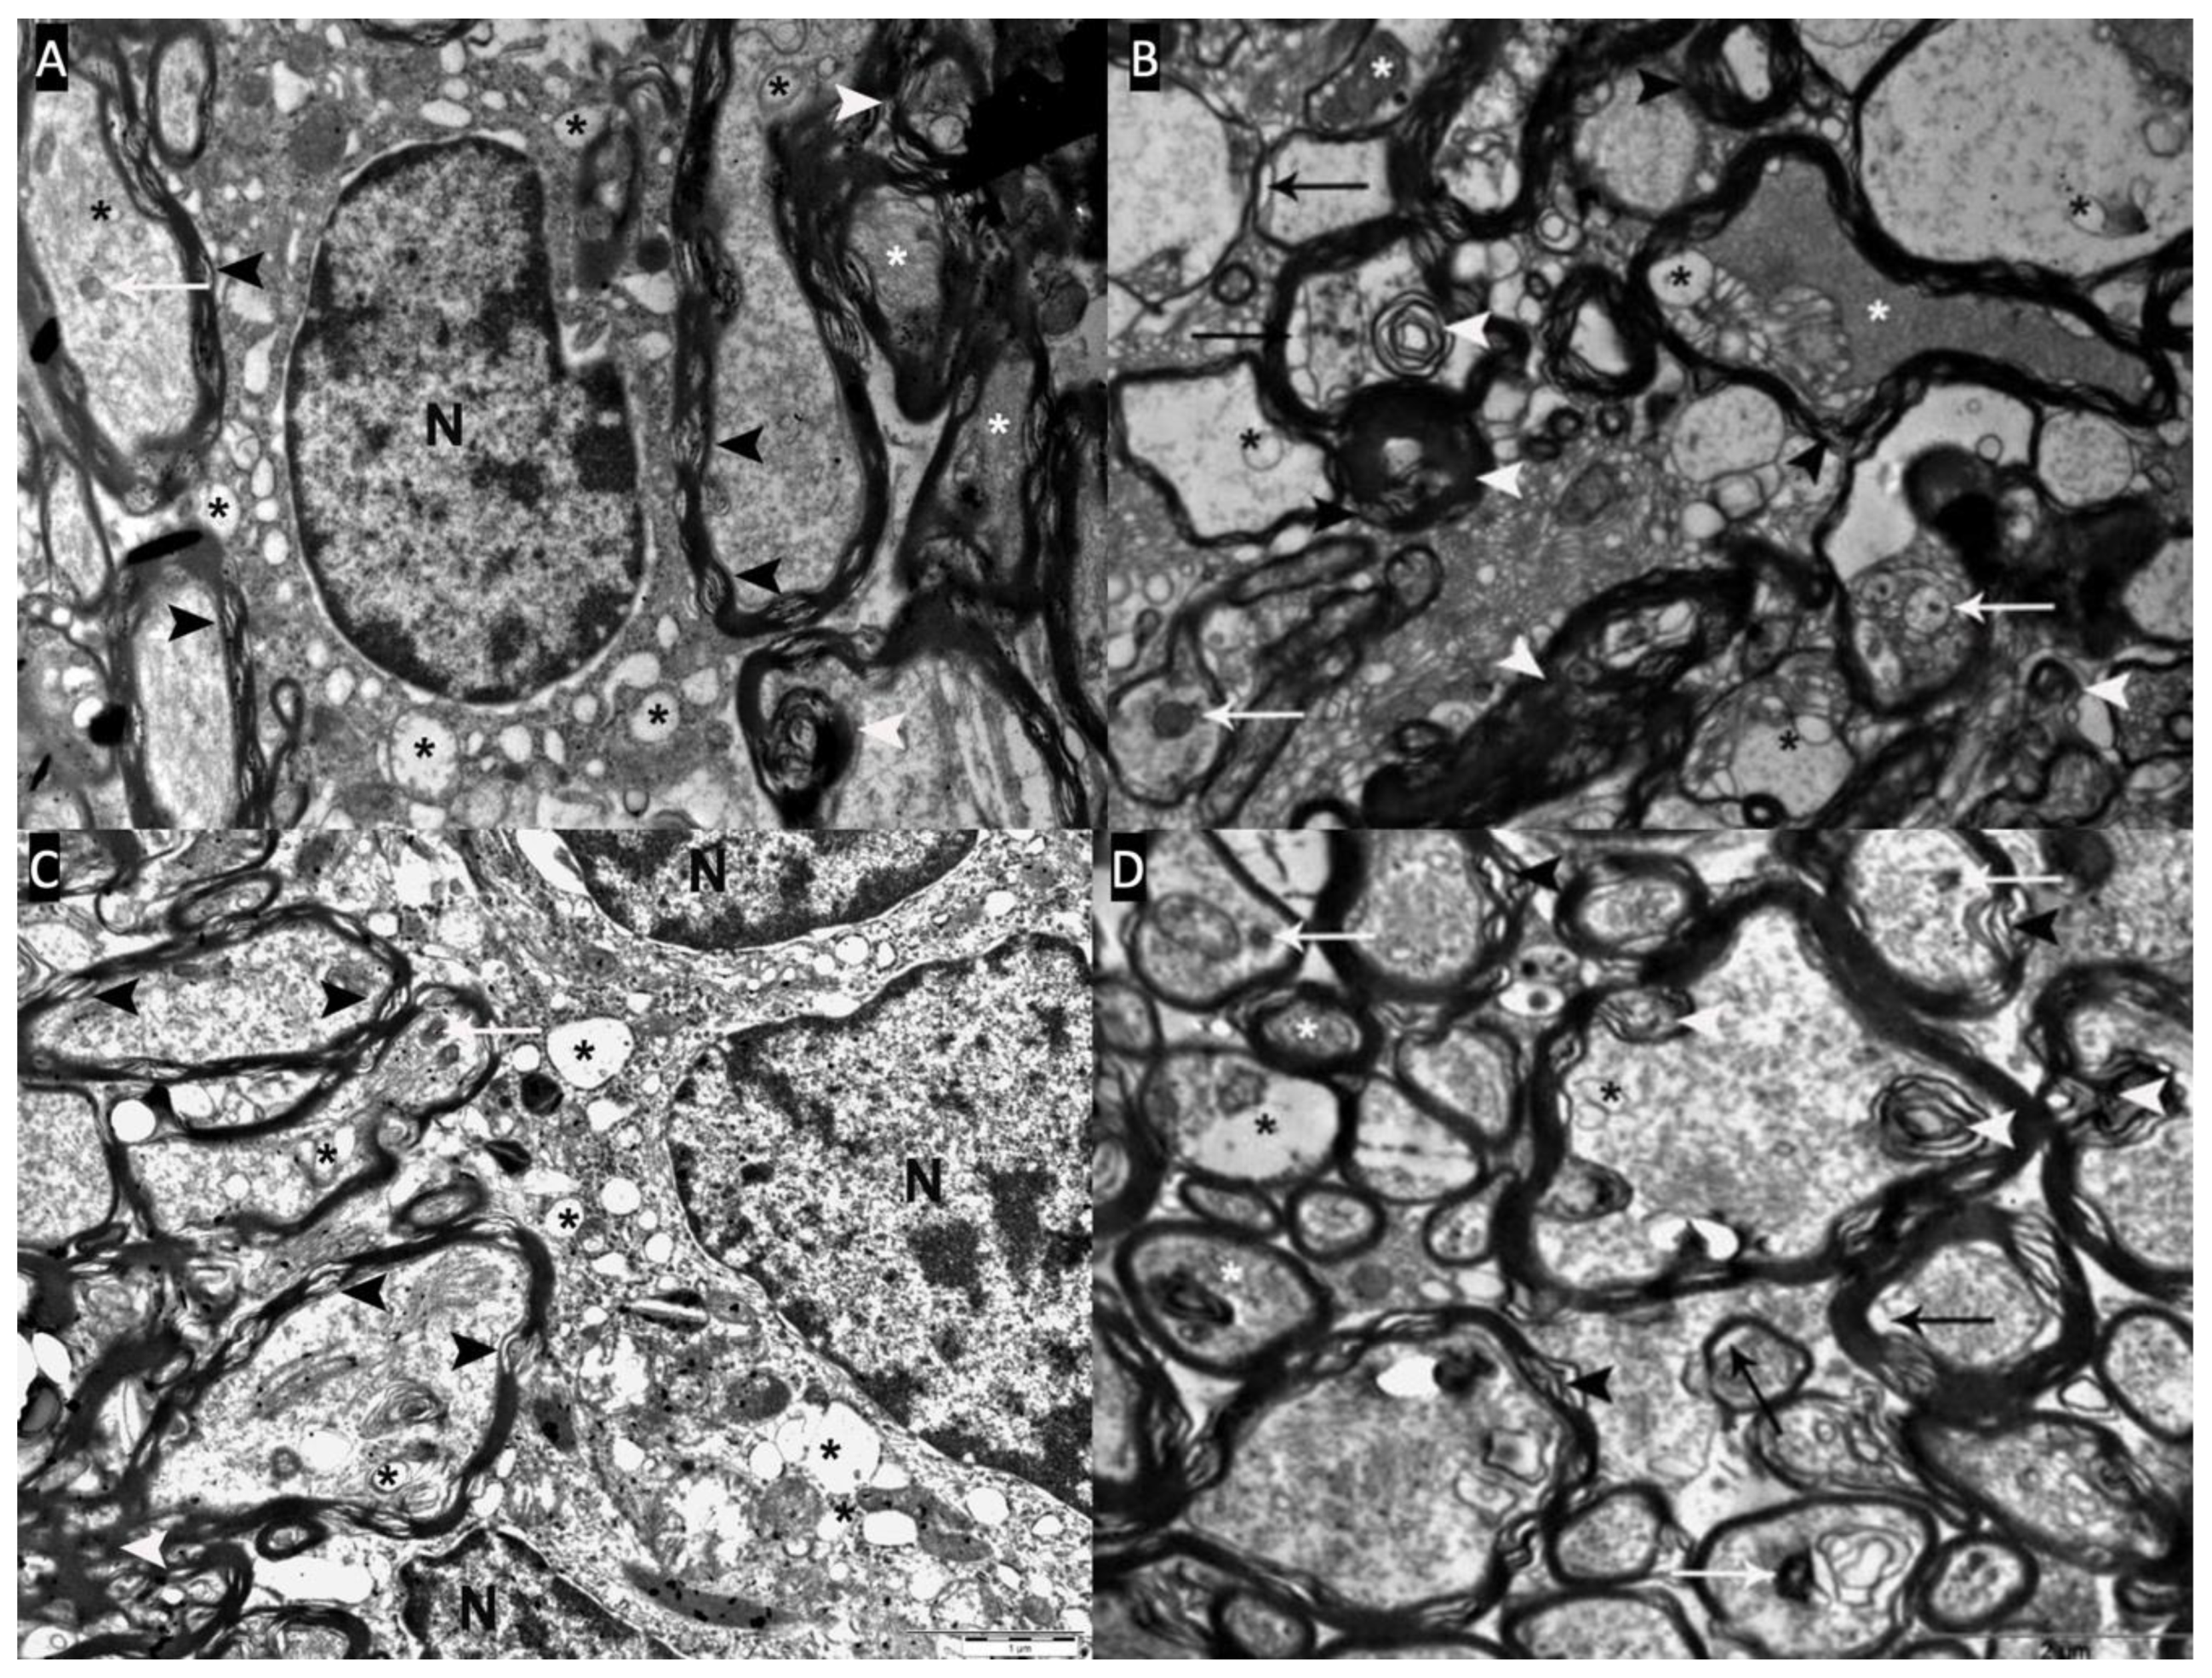

Seven out of 9 rats (77.8%) in the demyelination group (Group 2) showed severe pathological changes in which oligodendrocytes showed numerous heterochromatic nuclei and chromatin condensation. The cytoplasm of swollen oligodendrocytes appeared dense and uniformly granular due to scattered ribosomes. The cytoplasm also contained dilated mitochondria and cisterns of endoplasmic reticulum. The swollen axons appeared pale and enlarged with axolemmal expansion characterizing watery degeneration (axonal swelling). Several axons contained multilayered whorled masses, myelin debris, and blebs, which appeared to be arising from the inner layers of myelin. In some axons, their axoplasm was filled with a granular and dark material, described as dark degeneration (hyperdense axoplasm). The dark axons exhibited myelin changes such as lamellar separation and widening. Severe decompaction of lamellae made the myelin appear wave-like. Demyelinating changes such as loss of myelin (demyelination), myelin breakdown, and detached and vacuolated lamellae were frequently detected (Figure 5 A,B).

6 of 8 rats (75%) in the remyelination group (Group 3) showed severe pathological changes. In the remyelination group, the oligodendrocytes exhibited mitochondrial swelling, dilated cisterns of endoplasmic reticulum, and heterochromatic changes in nuclear morphology. The remyelination group also showed watery degeneration with vacuoles, dark degeneration, demyelination, separation of myelin lamellae, and whorl-like multilaminated myelin-like bodies in severely damaged axons (Figure 5 C,D).

Figure 5. A,B: Severe pathological changes(Type-III) are observed in the optic chiasm electron microscopy of the demyelination group (Group-2). Myelin bleb and debris (white arrowhead), axolemma-myelin separation (black arrow), myelin sheath loss and separation (black arrowhead), vacuoles (black asterisk) and inclusions (white arrow) in axons and oligodendrocyte cytoplasm, dark axons (white asterisk) and oligodendrocyte nucleus (N). C,D: Severe pathological changes(Type-III) are observed in the optic chiasm electron microscopy of the remyelination group (Group-3). Myelin bleb and debris (white arrowhead), axolemma-myelin separation (black arrow), myelin sheath loss and separation (black arrowhead), vacuoles (black asterisk) and inclusions (white arrow) in the cytoplasm of axons, dark axons (white asterisk) and oligodendrocytes nucleus (N).